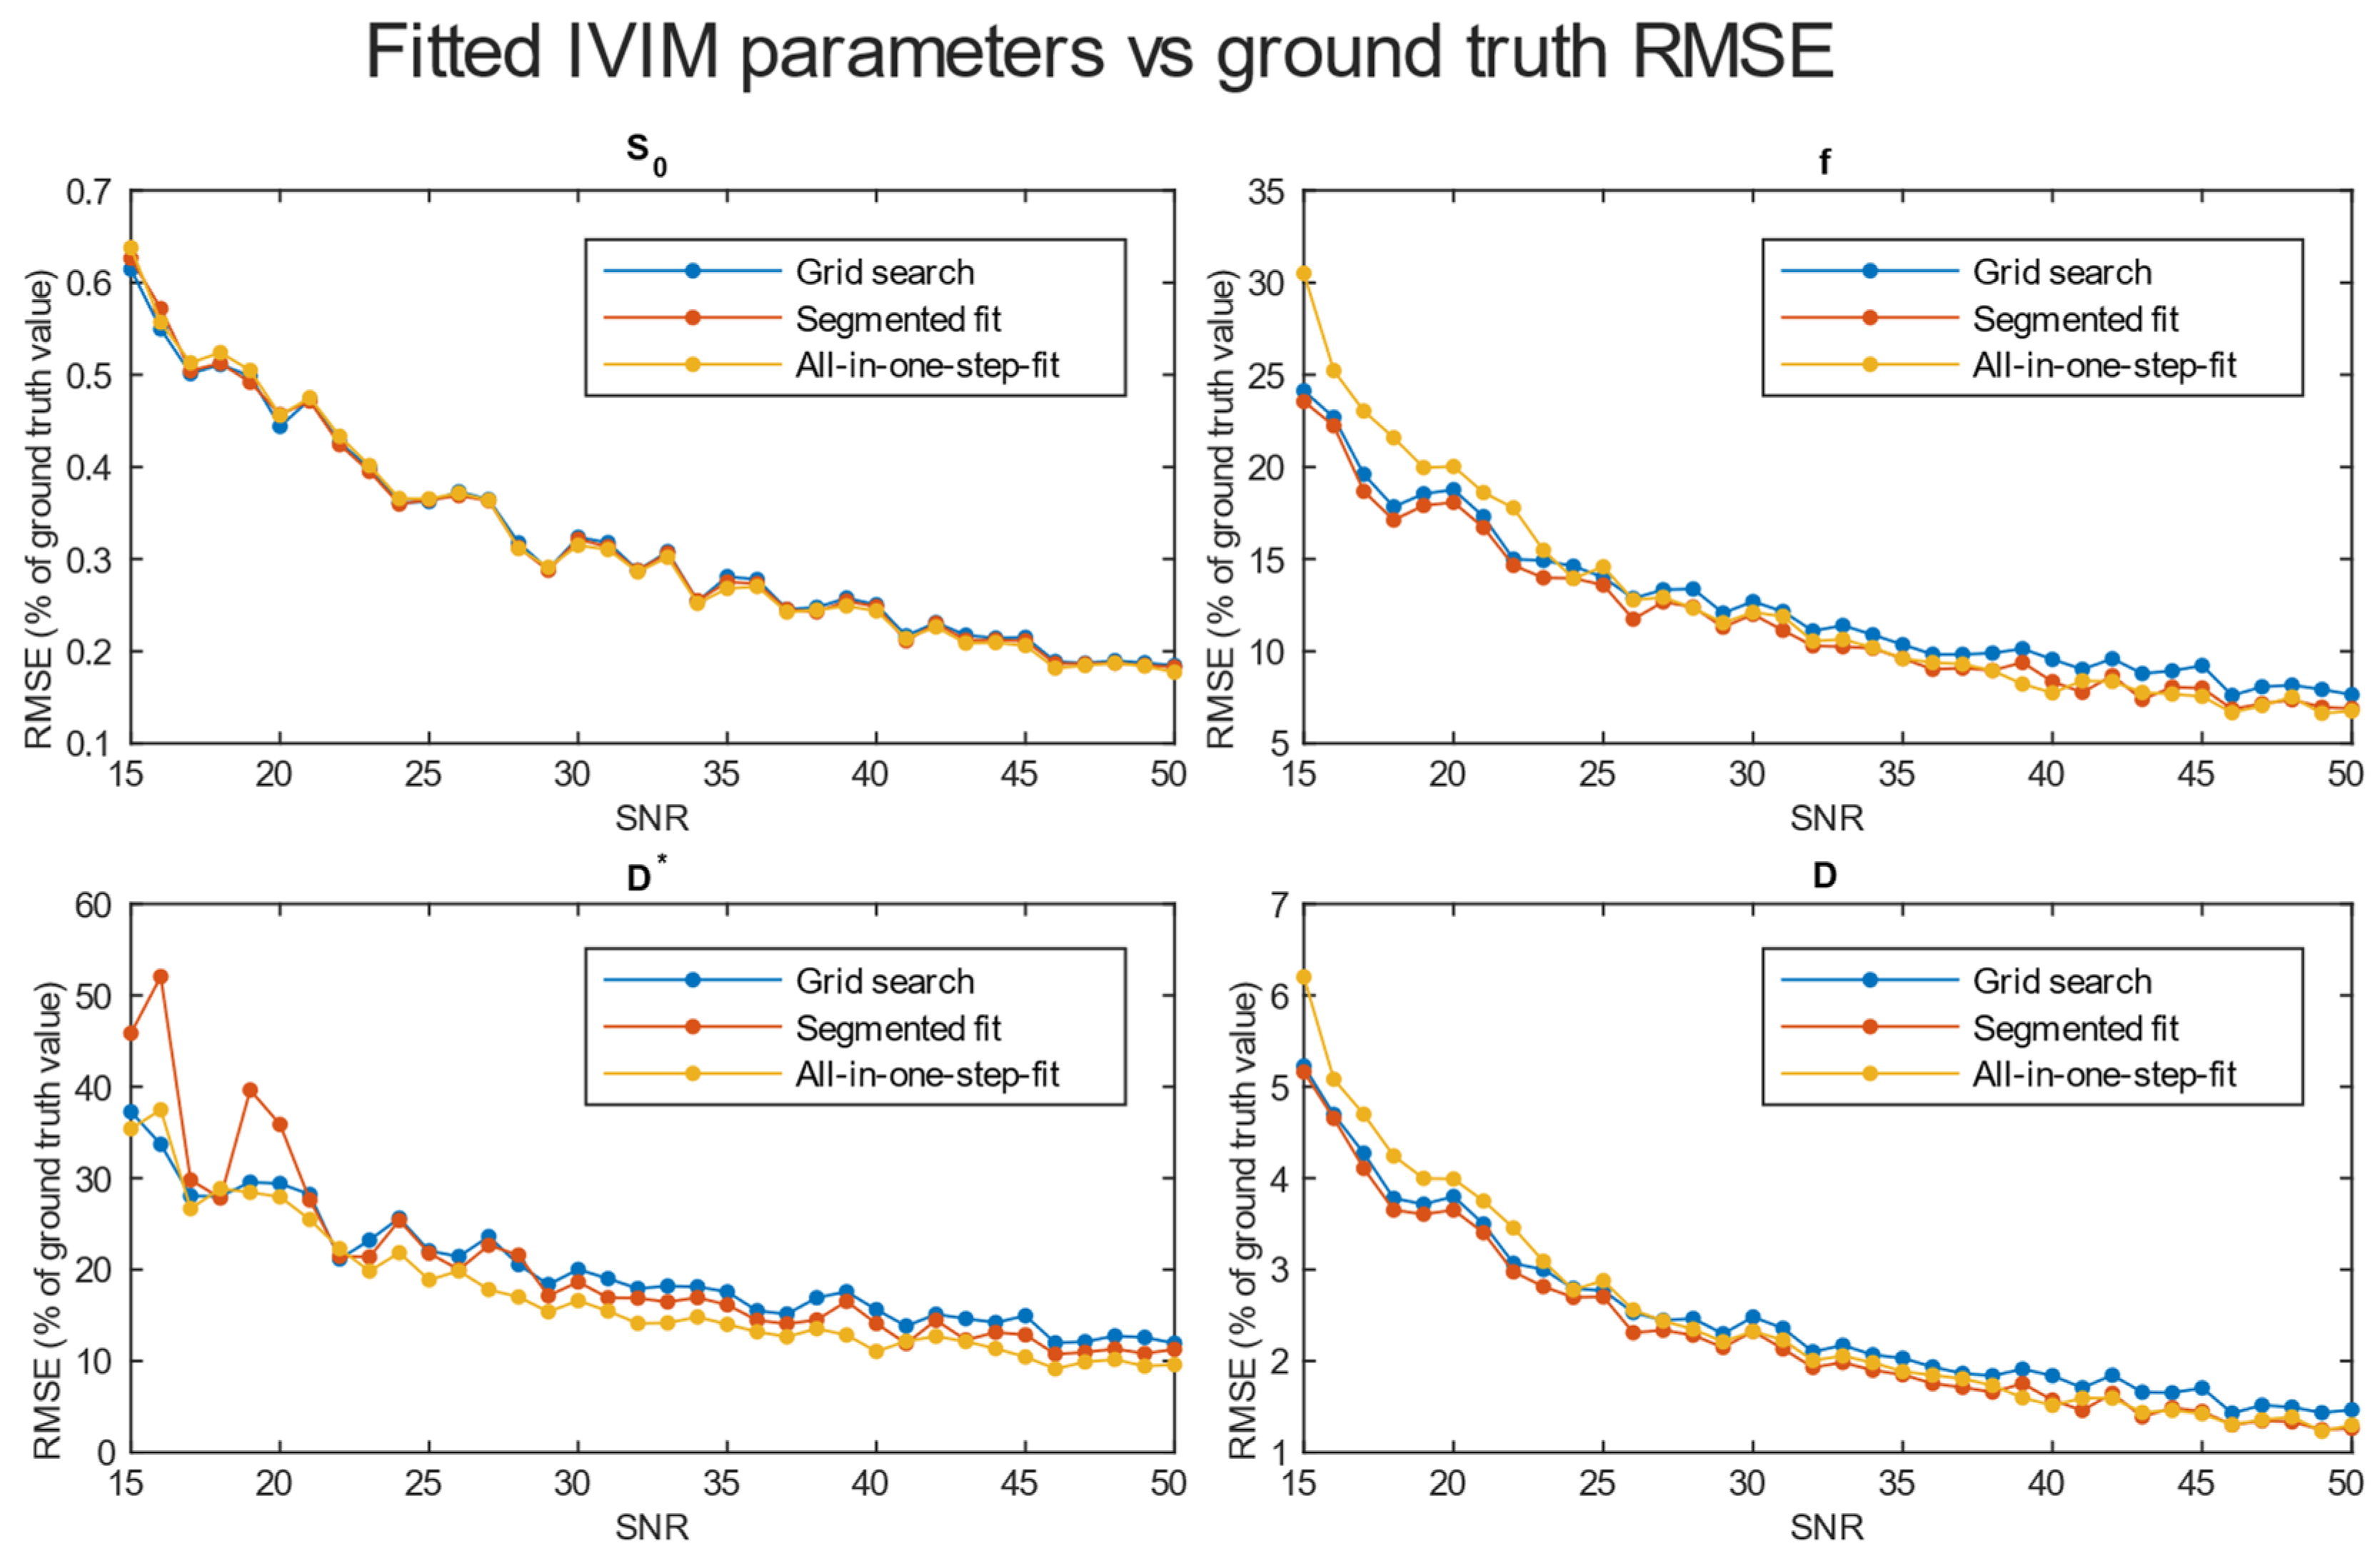

3.2. Evaluation of Accuracy

3.3. Results from Study